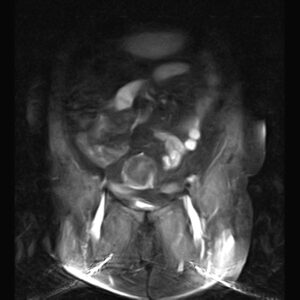

PELVIC MRI

( with & without contrast)

REPORT:

The pelvic inlet appears normal , with normal configuration of iliac wings and iliopsoas muscles.

No abnormalities are found in imaged bowel structures and there are no signs of wall thickening or mass lesions.

The adnexa appear normal on both sides.

The urinary bladder appears normal and has normal wall thickness.

The femoral heads are normally shaped and articulate normally with the acetabula they have normal bone marrow signal characteristics.

The muscles around the pelvis are unremarkable.

Sacroiliac joints are unremarkable.

– Multiple intra mural – subserosal myoma :

1. ( 40 x 45 mm ) in right side of fondus

2. ( 20 x 22 mm ) & ( 20 x 25 mm ) in right side of body

3. ( 48 x 55 mm ) in left side of body

– Both ovaries are atrophied & without follicles .